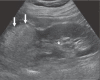

Angiomyolipomas (AMLs) are the most common benign renal tumours. Most of these neoplasms are found incidentally on imaging. However, symptomatic presentation does exist. Renal AMLs are typically composed of smooth muscle, blood vessels, and adipose tissue. Because of the abundant fat tissue, they give a characteristic appearance on imaging and are therefore easily diagnosed. However, sometimes they contain too little fat to be detected. This increases the difficulty in differentiating them from renal cell carcinoma (RCC). Management of AML is based on clinical presentation and should be individualized for every patient. Treatment modalities range from active surveillance to more invasive approaches.